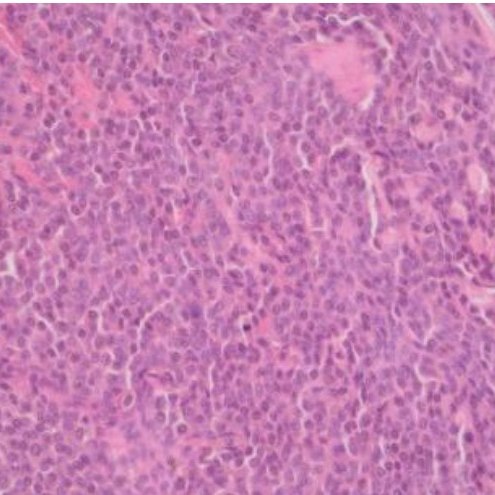

所幸,本篇的主角在我們進行細針穿刺(Fine Needle Aspiration)與細胞學檢查後,發現抹片下是充滿大量藍紫色顆粒的圓形細胞,為典型分化良好(Typical / Well-differentiated / Mastocytic)的皮膚型肥大細胞瘤,因此我們只需要沿著腫瘤外圍 0.5–1 公分的邊界切除即可。

後續病理切片的報告,也是如同我們術前的初步診斷,確診為皮膚型肥大細胞瘤,且手術邊界乾淨、未見腫瘤細胞出現。